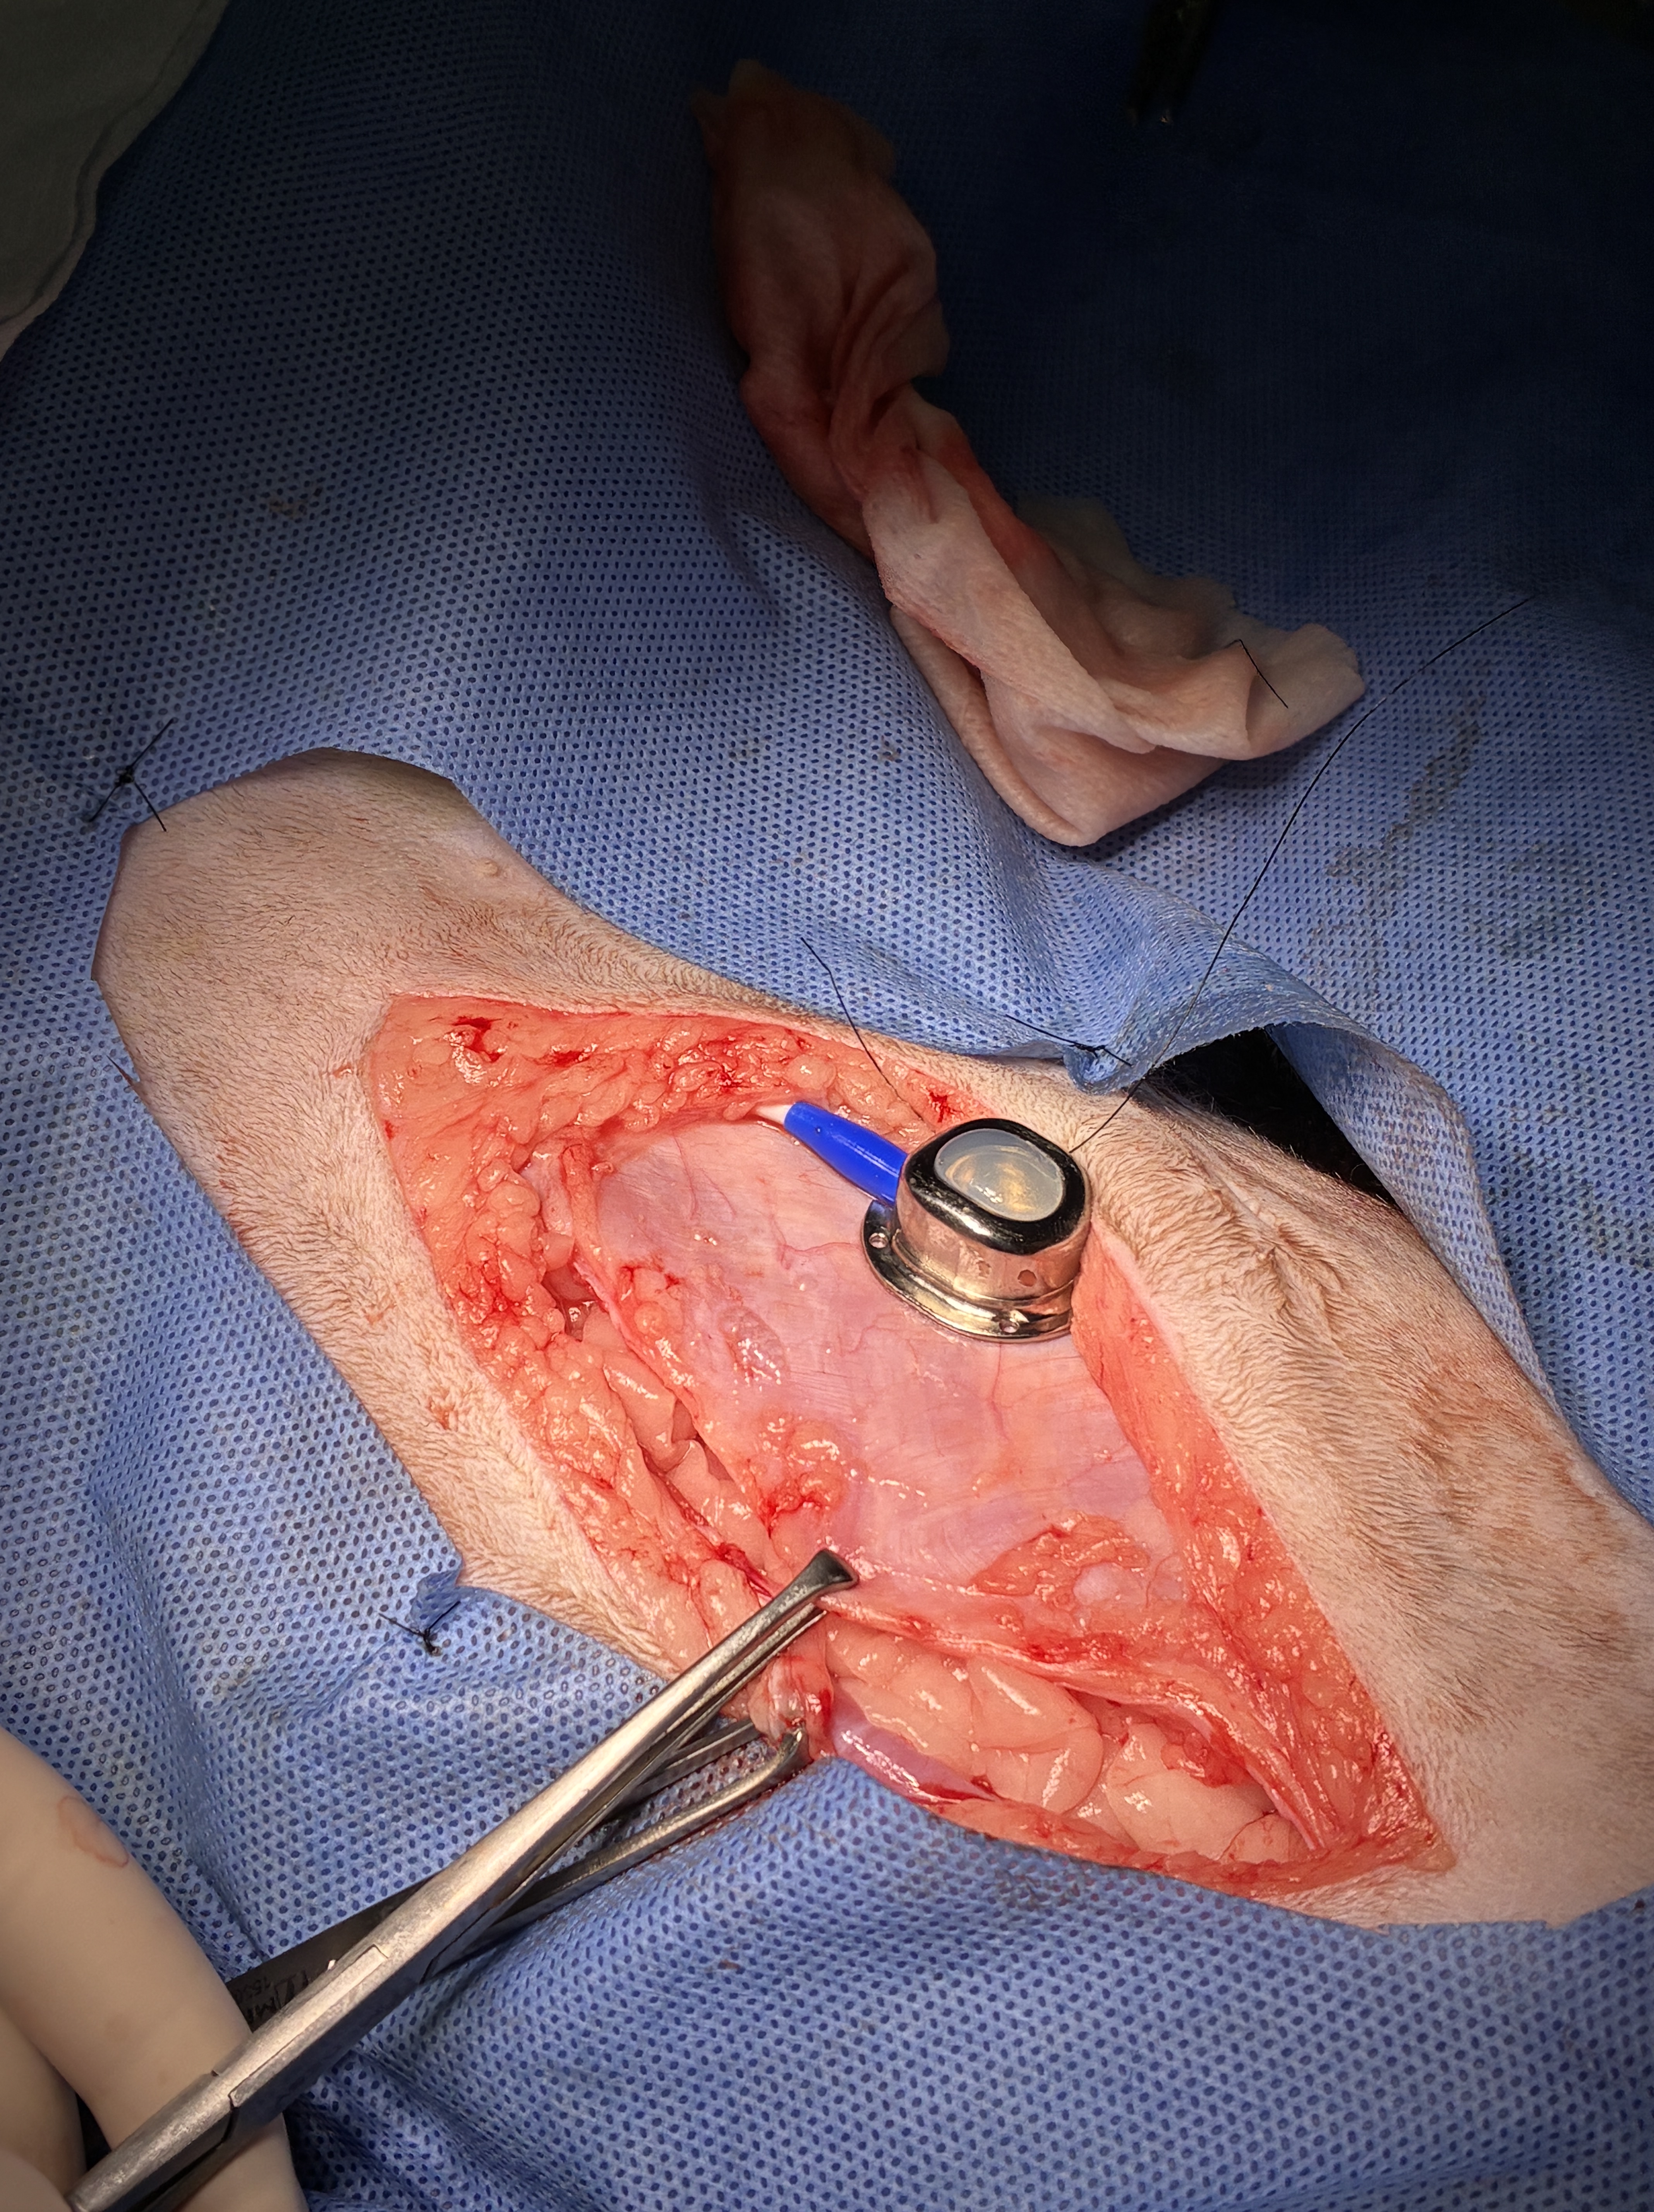

腎臓にバイパスの管を入れたところです。